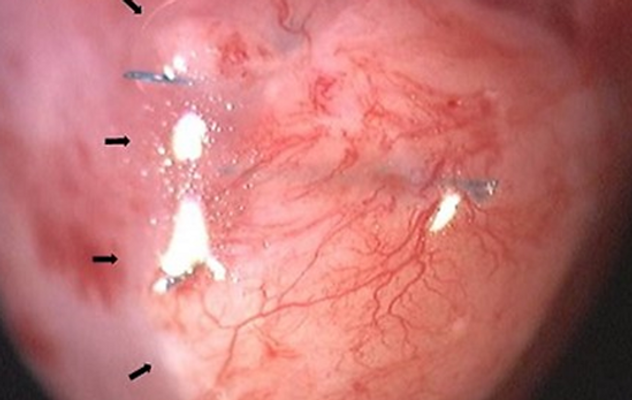

更容易的血管生成检测

用滋养的基质细胞直接进行血管自组装。